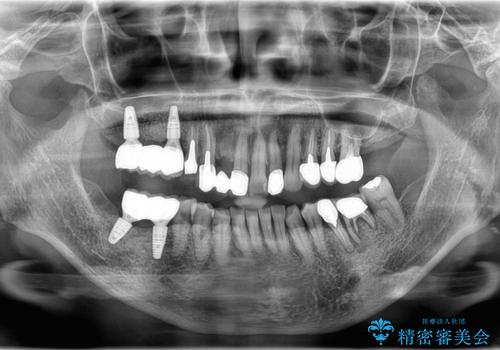

- 噛むと右の奥歯が痛い、何度も腫れを繰り返すとの事で来院された患者様です。

上顎は歯根破折と排膿が認められ、下顎も骨吸収により残せる状態ではないと判断し、抜歯後にインプラント治療(右上567、右下67)を行うことになりました。

骨吸収により上顎の骨量が少なかったため、インプラント埋入時にソケットリフトで骨補填材を填入も行いました。